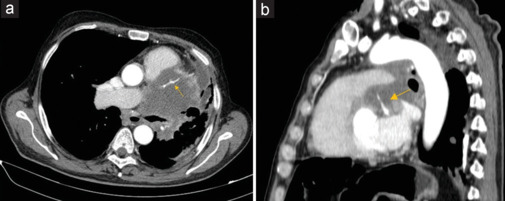

Cardiovascular disease and cancer constitute the most prevalent illnesses worldwide. Cancer patients show an increased risk of coronary artery disease not only due to shared cardiovascular risk factors, a pro-inflammatory and prothrombotic state induced by cancer itself, the cardiovascular toxicity of cancer therapy, or rarely, due to extrinsic compression of a coronary artery by the primary tumor or a metastatic lesion. Here, we present the case of a 59-year-old man with squamous cell carcinoma of the lung presented with asymptomatic diffuse ST segment depression and troponin T increase. Echocardiography revealed a large mass adjacent to the right atrium, atrioventricular groove, and basal segment of the anterior wall of the left ventricle, which the computed tomography scan showed to encase and probably compress the anterior descending coronary artery. Thus, the patient was diagnosed with acute coronary syndrome due to anterior descendent coronary artery compression by a neoplastic lung mass.